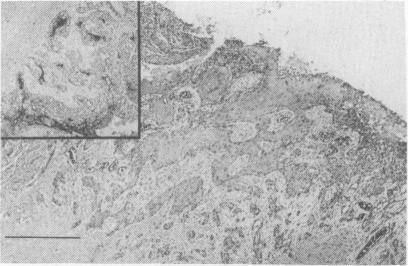

Squamous cell carcinoma arising in a subcutaneous dermoid cyst.

A case of malignant transformation to a squamous cell carcinoma in a long-standing subcutaneous dermoid cyst in a 44 year old man is presented. Malignant transformation in dermoid cysts is extremely uncommon and has never previously been recorded at this site. The need for adequate investigation and treatment of superficial midline lesions presenting in childhood is emphasized.